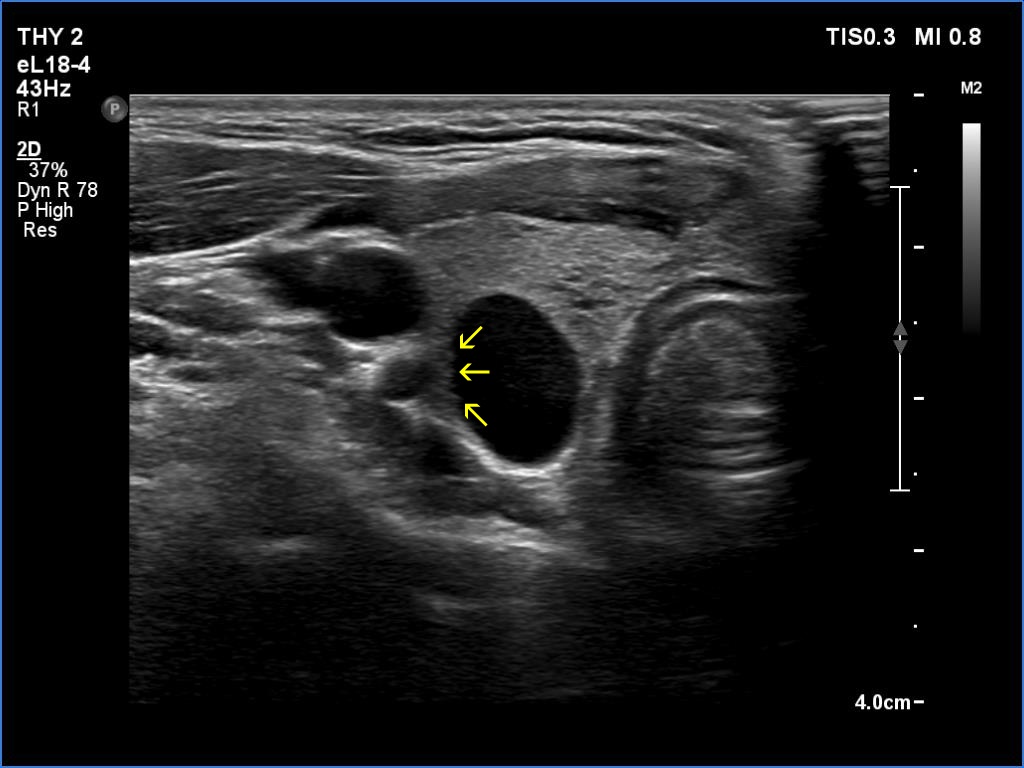

Transverse scan |

This is an almost completely cystic lesion, however it does not meet the criteria of a pure cyst. The wall thickening (yellow arrows) is ambiguous but there is a tiny solid-appearing area in the dorsal wall (red arrows). In systems which do not use the term 'almost completely cystic lesion', this nodule should be categorized as a peripheral-type cyst.